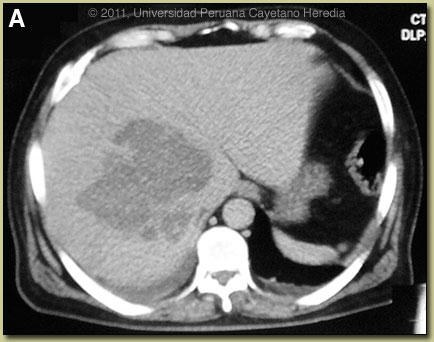

| Diagnosis: Liver abscess due to Entameba histolytica. |

Discussion: An ultrasound guided percutaneous aspiration [Image B] of the liver was performed and yielded 600cc of a brown-red material [Image C]. The material had very few PMNs but mostly cellular detritus. No trophozoites were seen in the abscess material; a typical situation which is a result of the invasive trophozoites being localized only to the periphery of the cavity in contact with viable liver tissue. Gram stain and all bacterial cultures were negative, ruling out a pyogenic liver abscess. ELISA performed on the aspirate looking for the galactose-lectin antigen of E. histolytica was negative but the procedure was performed after 7 days of metronidazole. Serum IgG and serum lectin was not performed due to patient economic constraints.